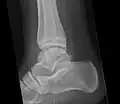

Ankle

Accessory bones at the ankle mainly include:

- Os subtibiale, with a prevalence of approximately 1%.[14] It is a secondary ossification center of the distal tibia that appears during the first year of life, and which in most people fuses with the shaft at approximately 15 years in females and approximately 17 years in males.[14]

- Os subfibulare, with a prevalence of approximately 0.2%.[15]

Os trigonum (further described below) may also be seen on an ankle X-ray.

Os trigonum

The os trigonum or accessory talus represents a failure of fusion of the lateral tubercle of the posterior process of the talus bone. Is estimated to be present in 7–25% of adults.[17] It can be mistaken for an avulsion fracture of lateral tubercle of talus (Shepherd fracture) or a fracture of the Stieda process. In most cases, Os Trigonum will go unnoticed, but with some ankle injuries it can get trapped between the heel and ankle bones which irritates the surrounding structures, leading to Os Trigonum Syndrome.[21]